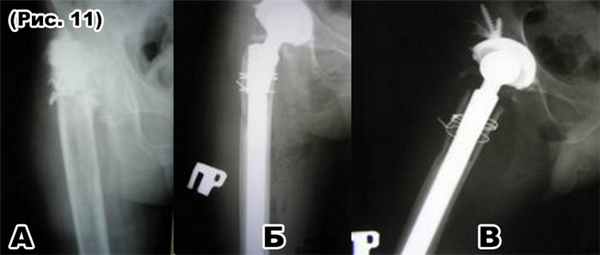

Операции при патологии тазобедренного сустава

а) фистулография: тотальная деструкция правого тазобедренного сустава;

б) и в) тотальноеэндопротезирование правого тазобедренного сустава ревизионным протезом после предварительной санирующей резекции сустава.